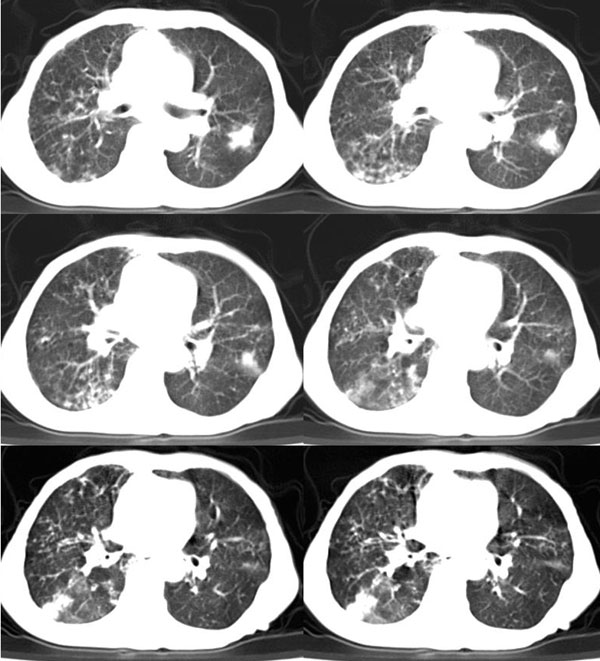

女:73岁;因一月前感冒后咳嗽,发烧,有大量脓痰,并且有恶臭味。

局部5毫米强化

补充_____伴双肺血行播散

谢谢辜兄为我们网站的兴旺所做出的杰出贡献!右下肺脓肿并双肺感染、右胸膜粘连。[emb21][emb20]

右下肺脓肿并双肺感染、右胸膜粘连。

右肺下叶示片状致密影密度不均,内见一空洞有宽液平,并可见壁结节周围示散在斑片模糊影,左下肺亦见一斑片模糊影,考虑 肺脓疡,肺癌不除外。

右下肺脓肿,两下叶,中叶支扩并感染,右侧胸膜肥厚粘连。